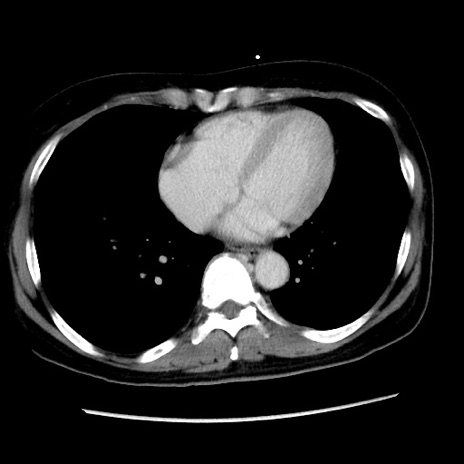

矢状断像

【症例】 50歳代女性

【主訴】 腹痛

【現病歴】前日生レバーを食べた。今朝に排便あり。 昼前に突然発症の腹痛を生じ、当院救急外来を受診した。

【既往歴】 子宮筋腫にてで子宮全摘後

【身体所見】 意識清明、腹部:平坦、軟、下腹部やや左を中心に圧痛・反跳痛あり、筋性防御あり

【データ】WBC 7800、CRP 0.07